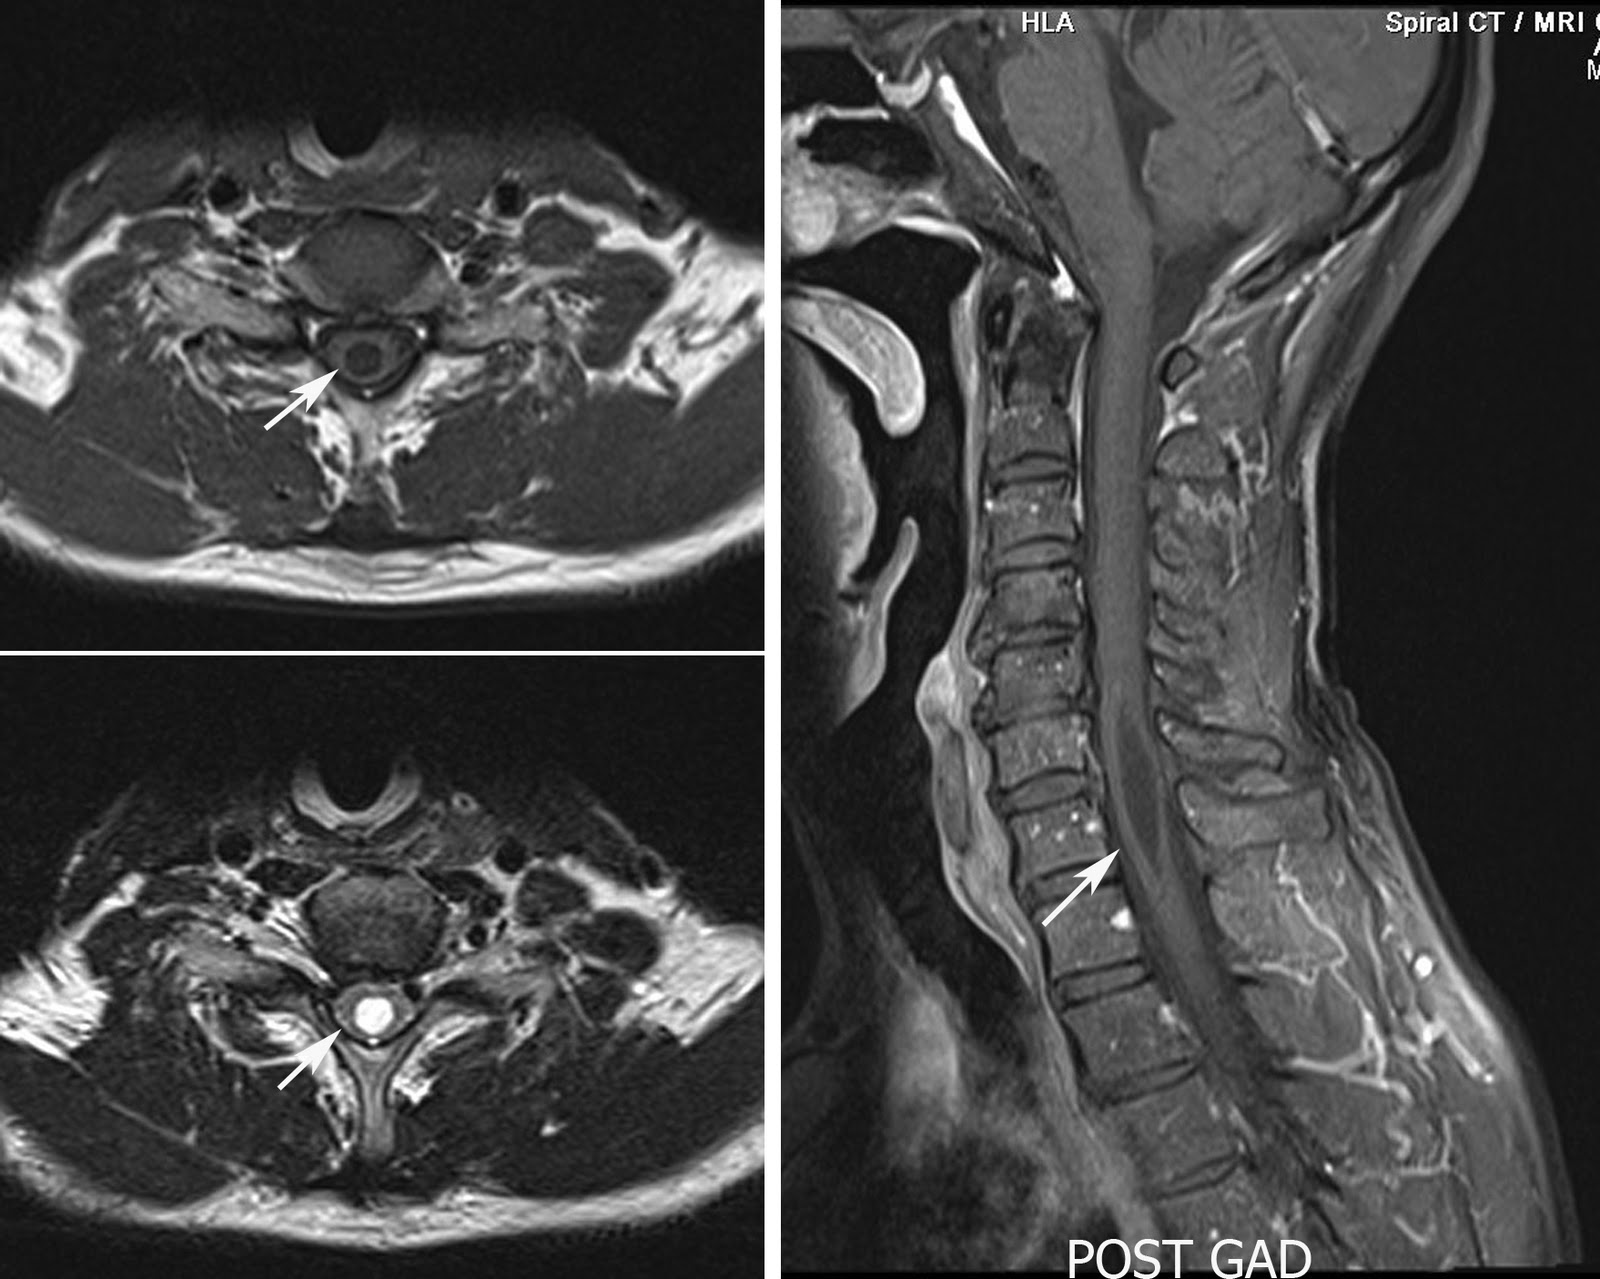

Syrinx - MRI

Cervical spine MRI in a 54 year old male patient showing focal dilatation of the central spinal canal with no enhancing focal lesion within the cord. The features are consistent with the focal syrinx.